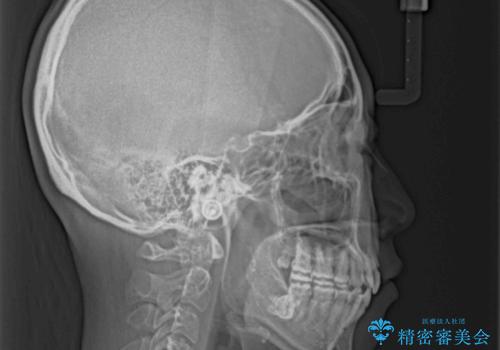

- 口元の突出感を気にして来院された患者様です。

診断の結果、上顎左右第一小臼歯4本抜歯により、叢生を解消するとともに口元を引っ込めていくことが望ましいと判断しました。

抜歯矯正による口元の改善にはワイヤー矯正が望ましいのですが、ダンサーとしての仕事を行っているため、インビザラインにて治療を行うこととしました。